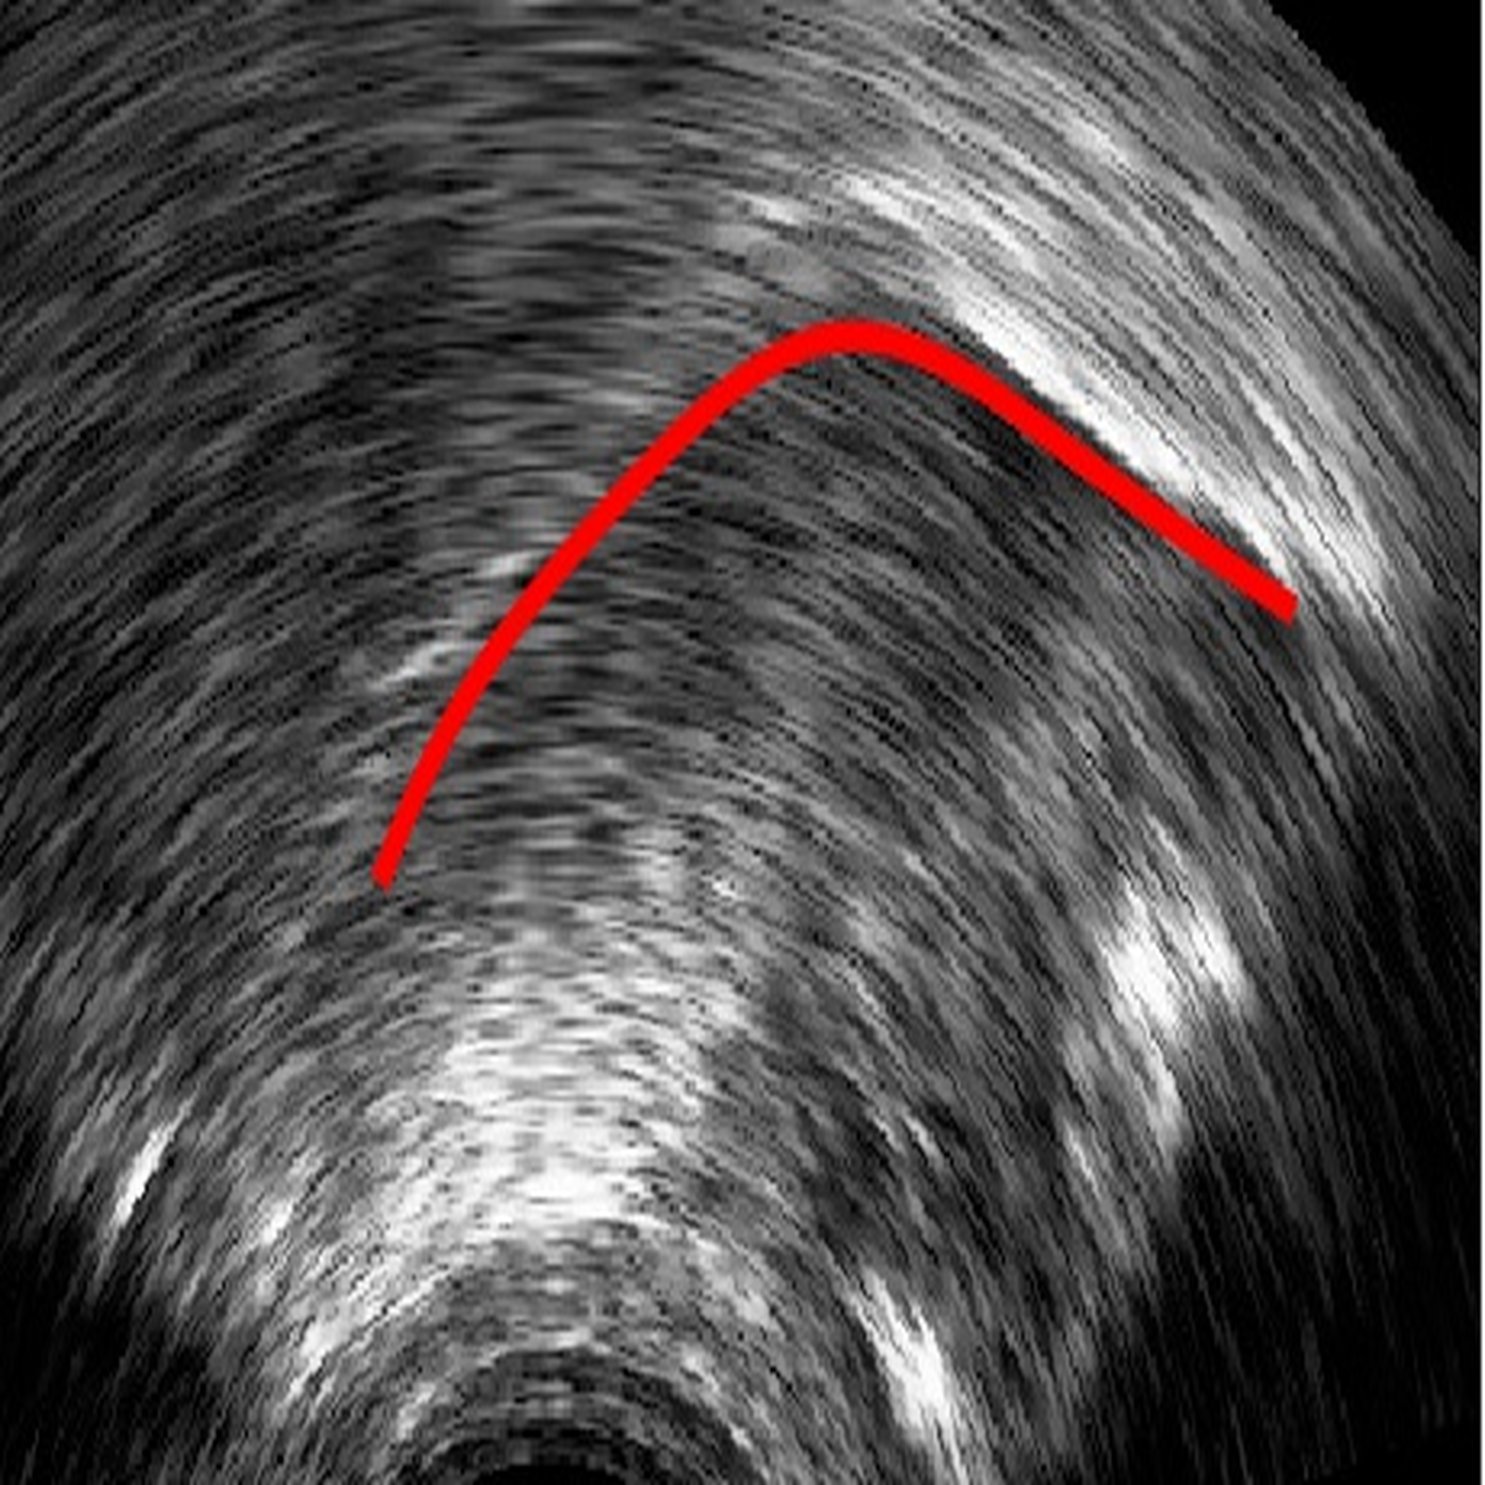

Ultrasound tongue imaging provides a non-invasive means for assessing tongue position and movement during speech production. However, the presence of speckle noise and irrelevant high contrast edges often degrades the usability of ultrasound images by obscuring the tongue surface [1]. Consequently, extracting tongue contours from ultrasound images remains a non-trivial task.

6 Error analysis

As the CNN is trained to identify the white edges directly corresponding to the tongue surface, additional or missing white edges due to bad image quality or speaker physiology can lead to failures in identifying parts of the tongue surface. In the absence of prior knowledge of plausible tongue shapes, the model will sometimes generate tracking errors when the white edge becomes blurry or interrupted. Similarly, bright edges in the image background are likely to be recognized as part of the tongue; tongue contours generated from image frames with these edges will likely suffer from implausible curvatures as interpolation in post-processing attempts to connect these regions. There some potential solutions to these problems, including incorporating temporal constraints on tongue contour variations across frames [3], or adding a smooth constraints that penalizes discontinuity of tongue contours, or introducing a strong prior probability of possible tongue locations. In data processing, these issues can also be mitigated by tuning the parameters in post-processing to match the needs of the specific dataset, and remaining errors can also be addressed through manual correction (as even then, the workload is considerably reduced relative to manually labeling all frames).